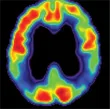

Il gruppo di lavoro, composto da scienziati del Banner Alzheimer's Institute in Arizona, della Boston University e dalla University of Antioquia, ha analizzato cervello, sangue e liquido cerebrospinale di 44 individui tra i 18 e i 26 anni che non presentavano segni clinici dell'Alzheimer. La scoperta è stata sorprendente: quasi un terzo delle persone testate presentava la mutazione di un gene chiamato presenilina (PSEN 1). Non solo. In questi soggetti l'attività elettrica nell'ippocampo (area responsabile della memoria) e nel paraippocampo era decisamente superiore a quella rilevata in persone con il gene non mutato, il volume cerebrale in altre aree del cervello minore e la concentrazione nel liquido cerebrospinale, della proteina beta-amiloide (principale responsabile dello sviluppo dell'Alzheimer), maggiore.